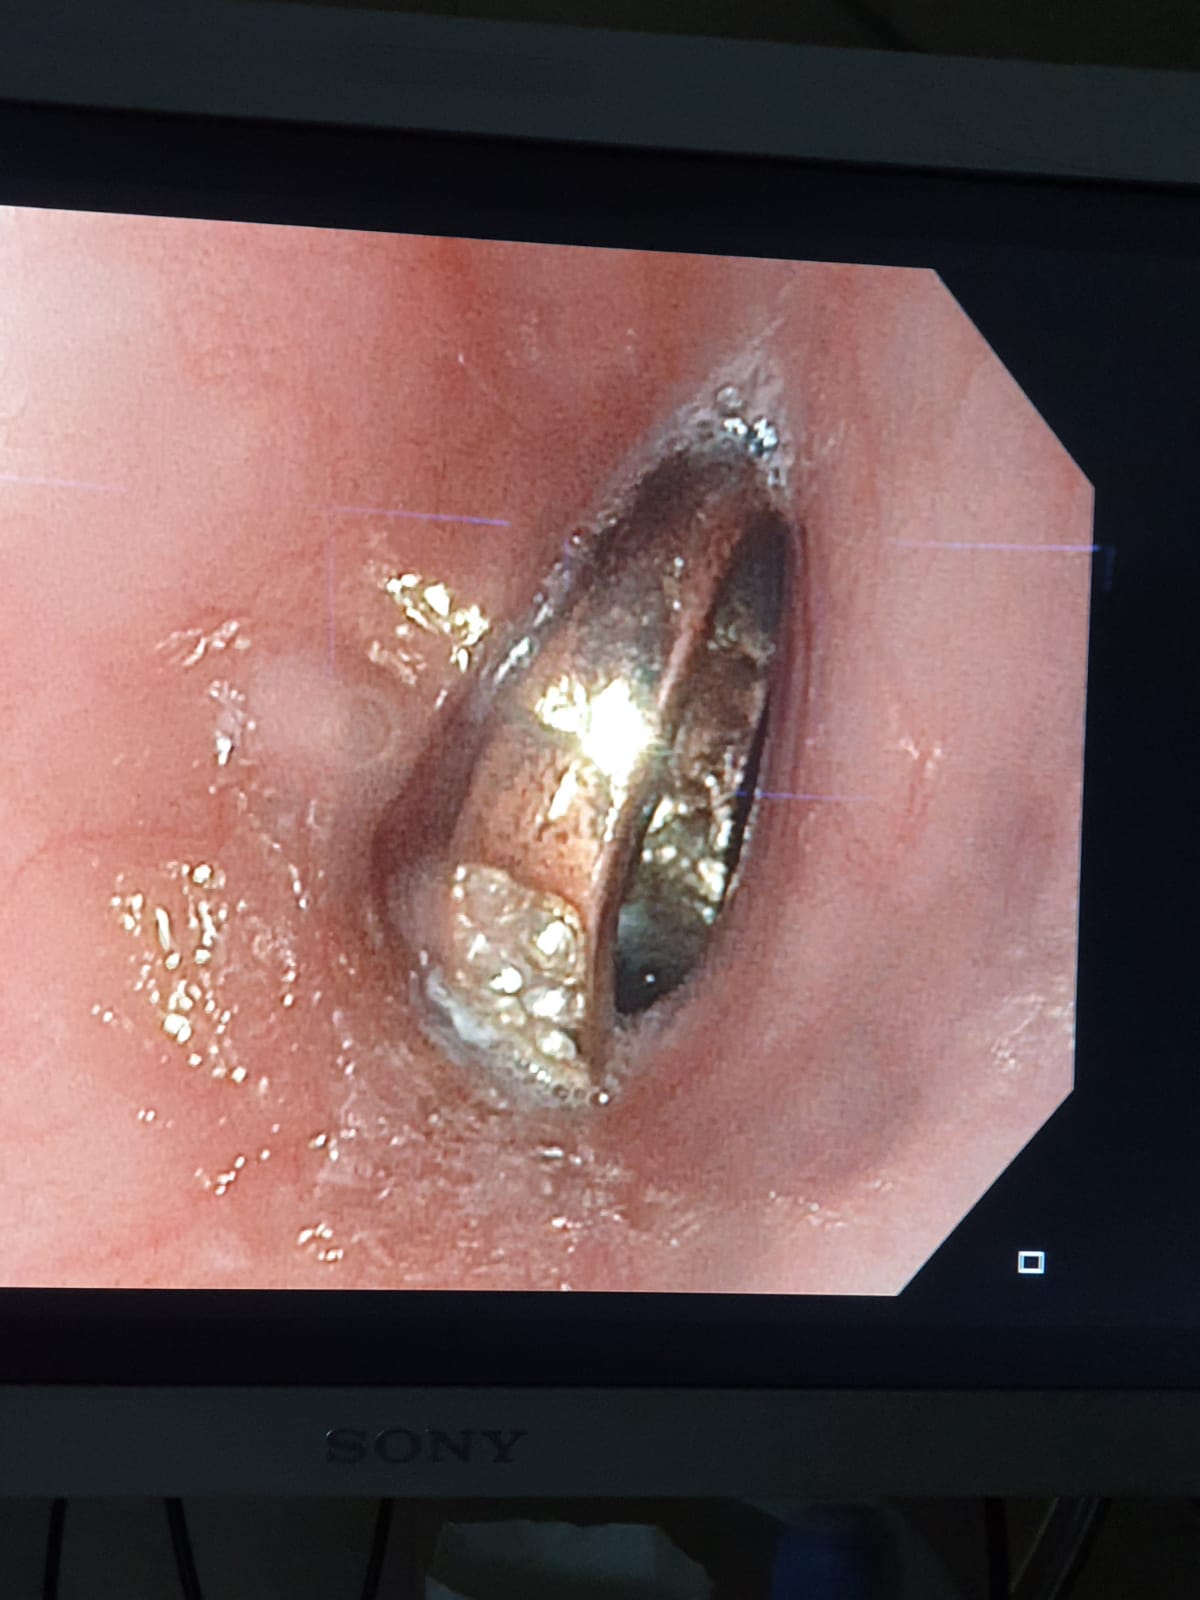

מי שביצע את הפעולה בהרדמה כללית ובחדר הניתוח, היה רופא גסטרו ילדים של המרכז הרפואי זיו, ד"ר ביאן הינו, בעזרת אחראית מכון גסטרו האחות שרי טרבלסי וצוות חדר הניתוח.

ד"ר ביאן הינו אמר: "ילדים בולעים גופים זרים שונים, אבל יש כמה שדורשים התייחסות מיוחדת והוצאה אנדוסקופית מיידית כשהם בטווח השגה. במקרה הזה, הילדה בת ה-6 בלעה טבעת שנתקעה בושט ולכן נדרשה הוצאה אנדוסקופית בהרדמה כללית בחדר. על ההורים והמטפלים מוטלת החובה לשמור היטב על ילדיהם מסכנות אלו".